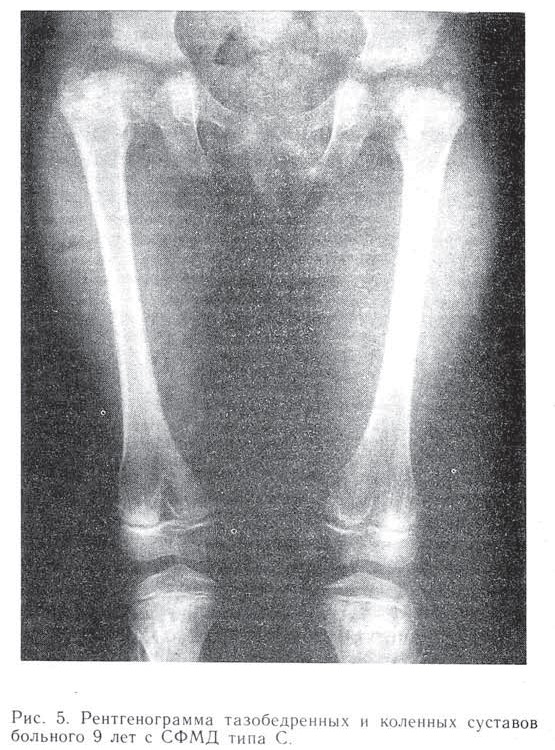

Рис.5 Рентгенограмма тазобедренных и коленных суставов больного 9 лет с СФМД типа С

Coxa vara (100°); структура метафизарных отделов бедренных и большеберцовых костей неравномерная, крапчатая, контуры неровные.

Тип С. К этому типу нами отнесены 32 больных, у которых изменения в позвоночнике, метафизах и ростковых зонах длинных костей встречались в различных сочетаниях и имели разную степень выраженности. Однако ни резчайшей coxa vara, как при типе А, ни языкообразных тел позвонков, как при типе В, у этих больных не было. Наиболее часто отмечались выраженные изменения структуры метафизов длинных костей.

Третью возрастную группу составили 15 больных. Шейки бедер у них были умеренно укорочены, расширены, шеечно-диафизарный угол составлял 90—100°. Изменения в метафизах у 9 детей были нерезкими, имелась тенденция к восстановлению структуры кости в процессе роста ребенка (рис. 5). У 7 больных наблюдалась резкая перестройка метафизов, что сочеталось с выраженным уплощением тел позвонков. Уплощение сохранялось и у взрослых, тогда как структура метафизов восстанавливалась.